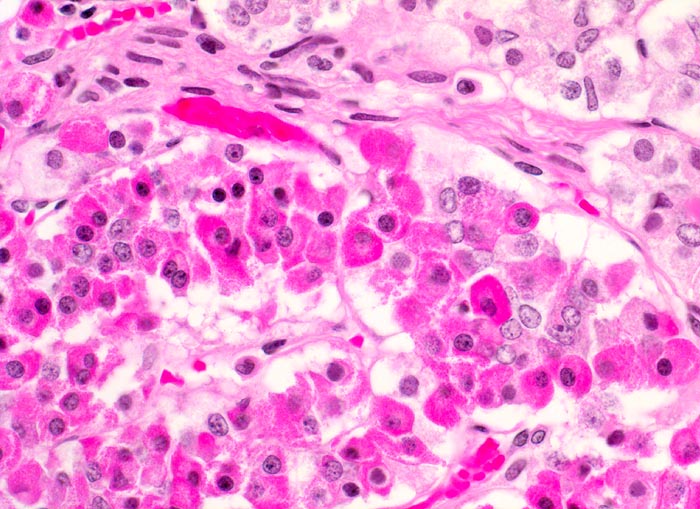

Hypophysenadenom

Die Ausstriche sind zellreich und die Zellen sind einzeln, in papillären Verbänden oder Gruppen angeordnet. Zytoplasma ist reichlich vorhanden und ist abhängig vom Typ des Adenoms eosinophil oder basophil. Im Gegensatz zum bunten Zellbild einer normalen Hypophyse wirken die Zellen des Adenoms eher gleichförmig. Die Kerne sind rund und monomorph, das Chromatin ist fein oder Pfeffer und Salz artig. Nukleolen sind meist klein, können aber auch prominent sein. Dignität und funktionelle Eigenschaften sind zytologisch nicht bestimmbar.

Die Differentialdiagnose umfasst Oligodendrogliome und hoch differenzierte Adenokarzinommetastasen.